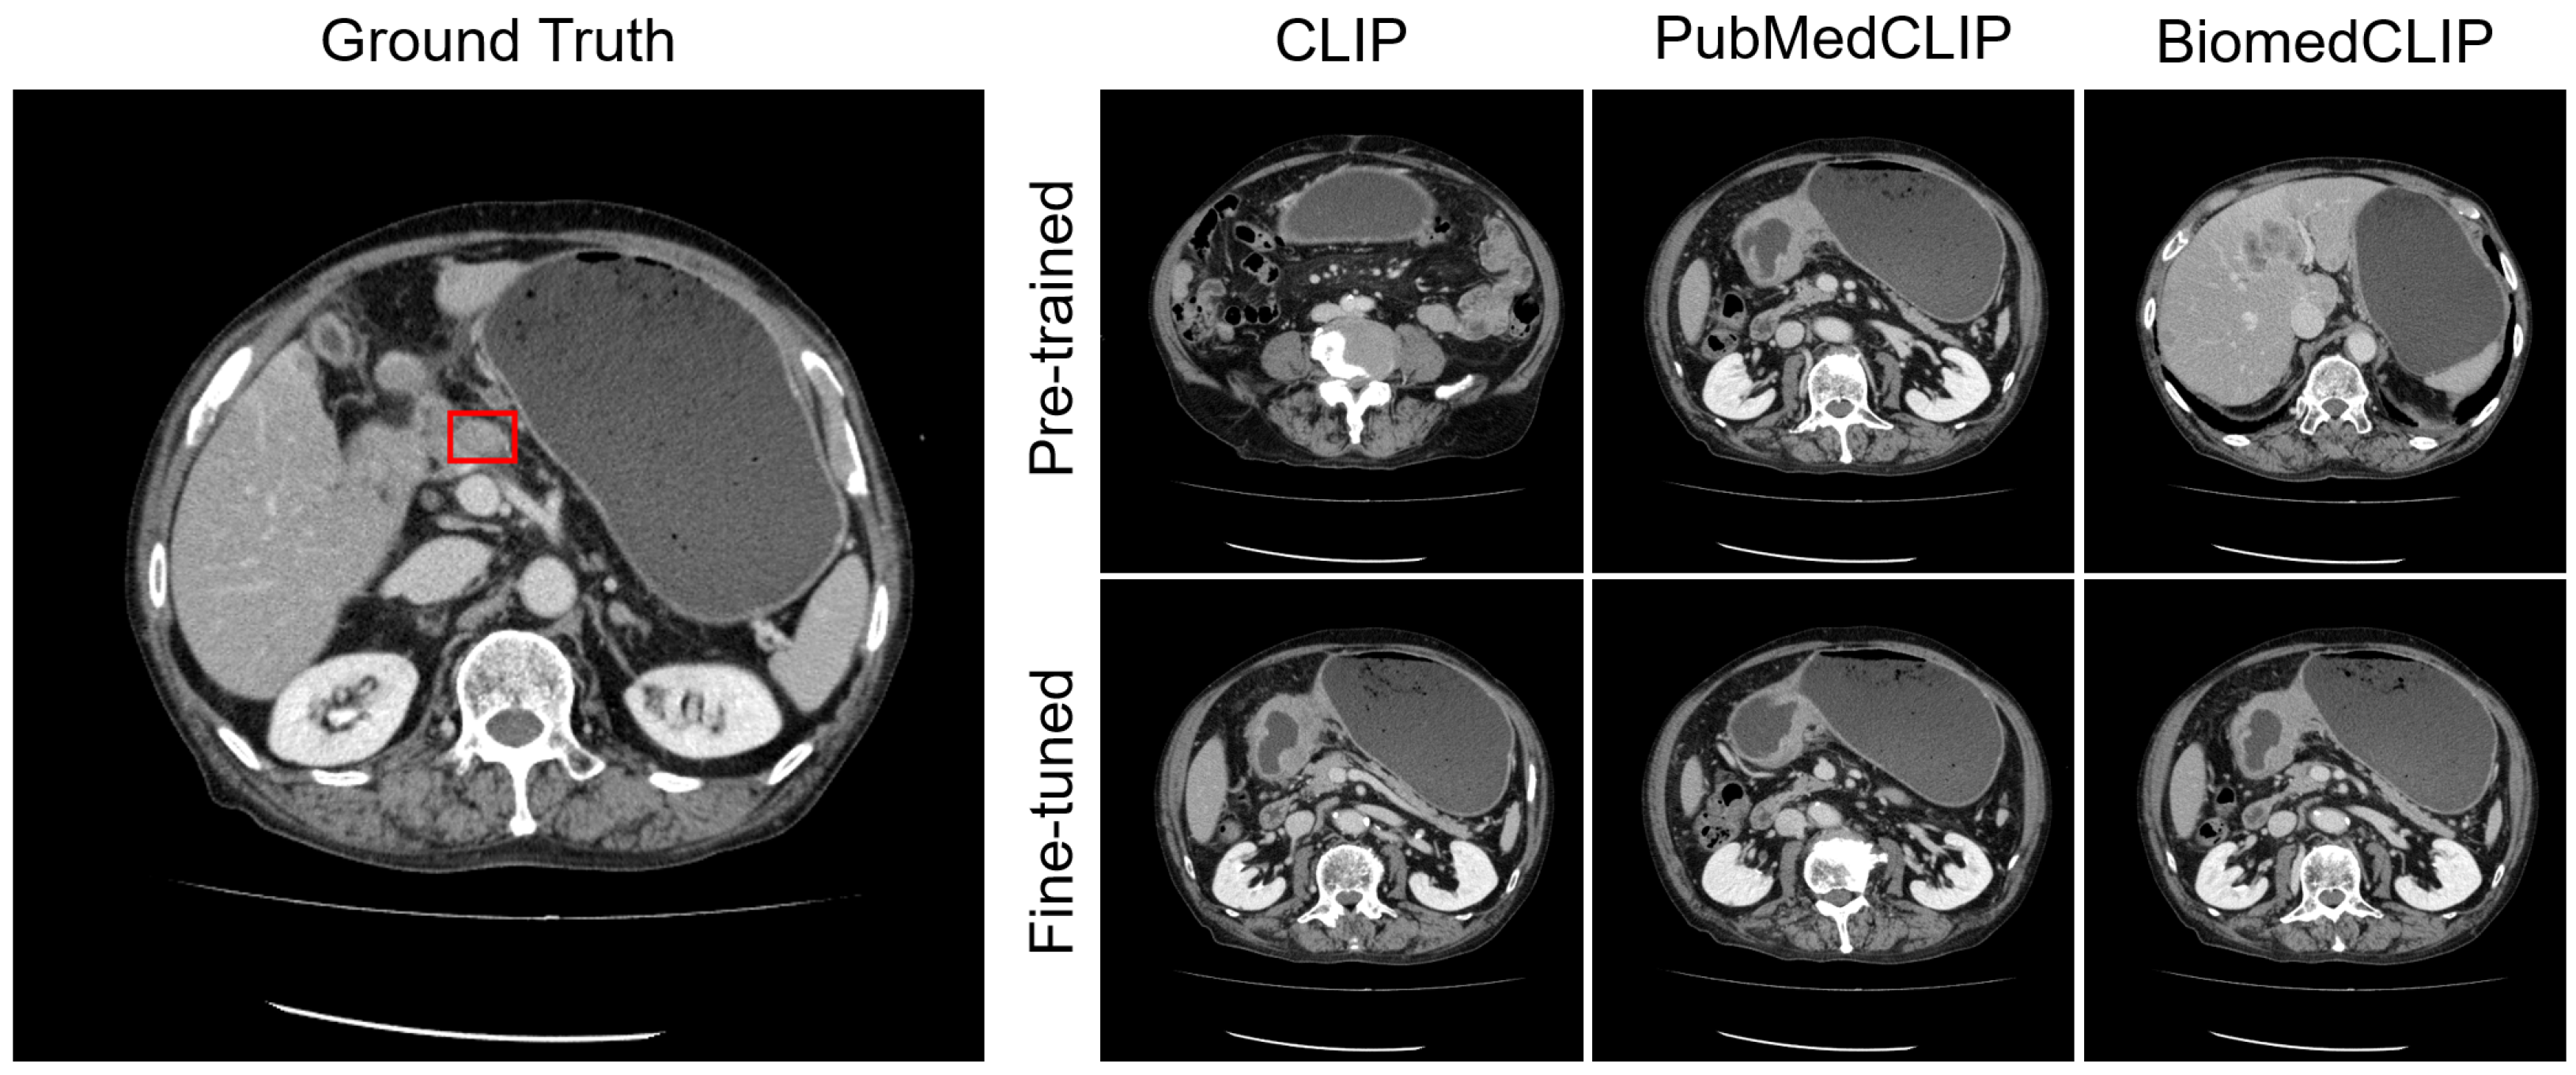

4.4. Visualization

Appendix C. Visualization

Appendix C.1. Lesion Awareness